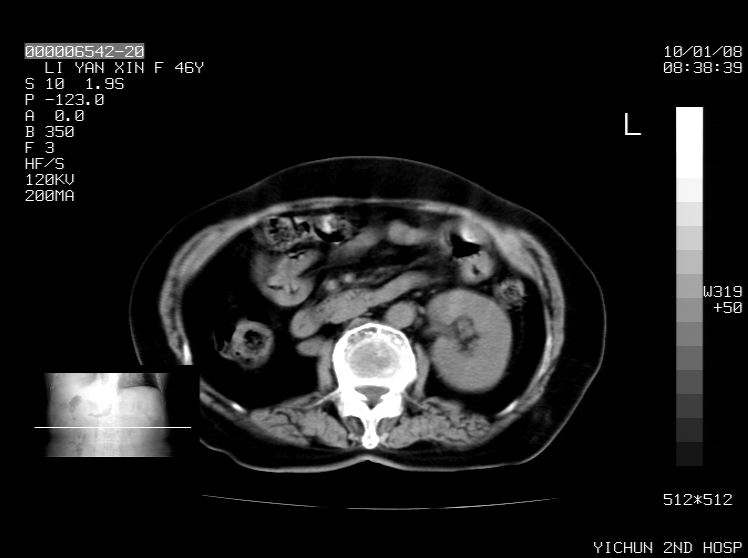

右侧膈膨升,胆囊壁厚,右侧肾脏缺如。病史?

右侧膈膨升,肝内钙化灶,胆囊壁厚,右侧肾脏缺如。病史?

右膈膨出,肝脏变异,肝内钙化,右肾缺如,脾大。

右侧膈膨升,胆囊壁厚,右侧肾脏缺如,增强,腔静脉旁是否是移位肾

肝脏变异致膈升高,肝左叶肝内胆管结石.右肾萎缩,左肾代偿肥大.

胆囊ct未见确切异常,请结合b超。右侧肾窝未见确切肾脏影,右肾萎缩?异位?

右侧膈膨升,肝内钙化灶,胆囊壁厚,右肾萎缩或发育不良。